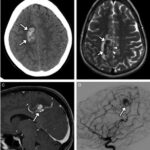

En los casos de personas sin patología vascular subyacente, las hemorragias intraparenquimatosas se localizan con mayor frecuencia en los ganglios basales y el tálamo. Un caso como este se obtuvo en la literatura, correspondiente a una mujer de 23 años que sufrió una hemiplejía completa. Se le localizaron cantidades considerables de cocaína en el análisis de orina. La RM evidenció una isquemia en la rama MCA derecha con afectación de los ganglios basales(17) (ver Imagen 7).

Otro caso que conviene referir es el de una mujer de 19 años, quien acudió al servicio de guardia por dolor de cabeza agudo. Se le realizó una TC que mostró una hemorragia intraventricular con un posible componente parenquimatoso cerca de la pared del ventrículo derecho, a partir del abuso de cocaína en combinación con alcohol (ver Imagen 8). De igual modo, la angiografía evidenció una malformación arteriovenosa coroidea alimentada por la arteria coroidea lateral posterior(17) (ver Imagen 9).